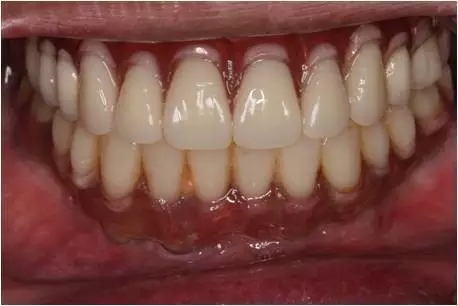

患者男性,51歲,全口無牙,下頜骨量尚可,上頜后牙區(qū)上頜竇底剩余骨高度嚴(yán)重不足,前牙區(qū)牙槽突較豐滿,主訴希望全口種植固定義齒修復(fù)。于2015年 9月接受種植治療:上頜采用All-on-4種植方案、下頜采用常規(guī)種植6顆種植體方案,種植后行即刻修復(fù)(圖1-2)。